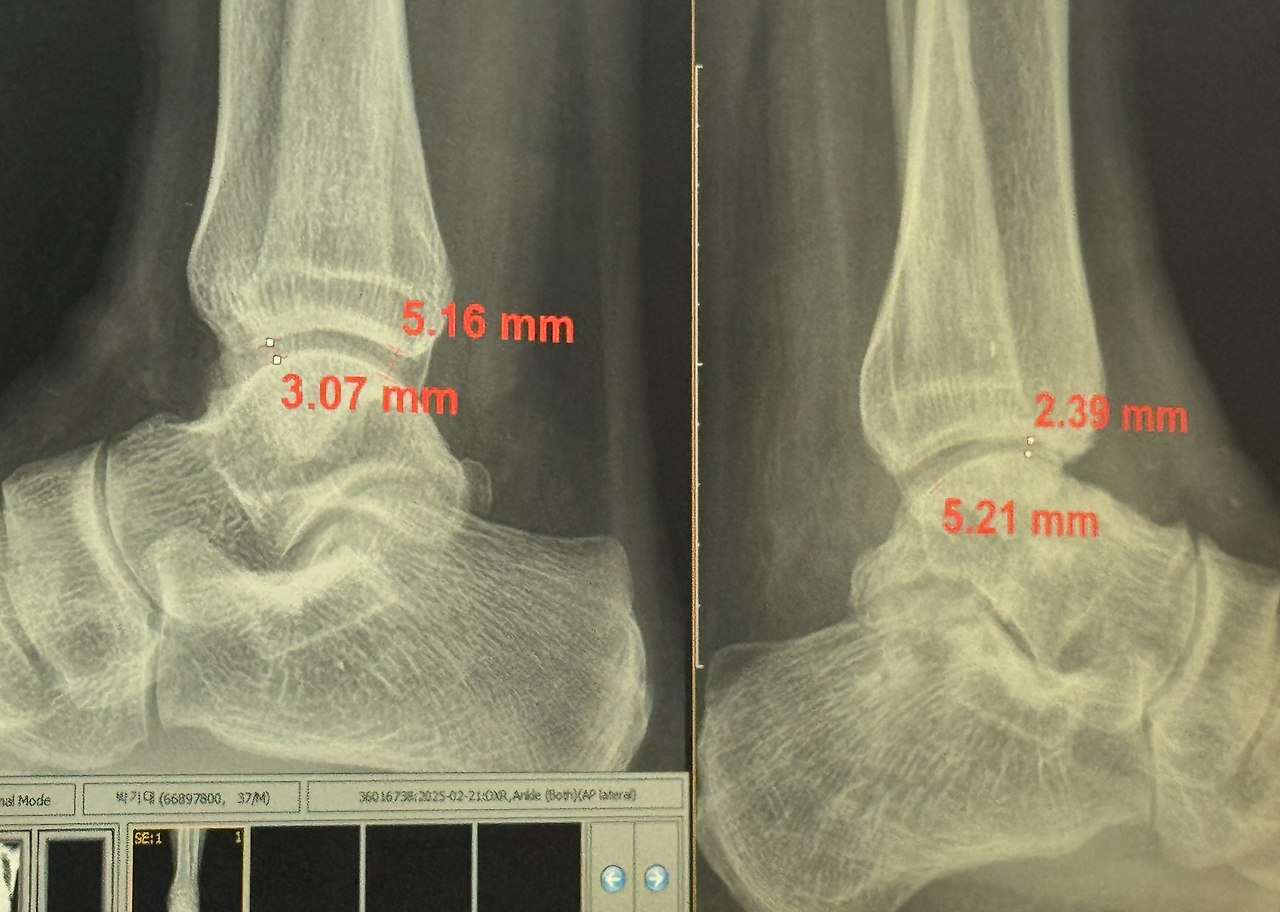

의사 선생님이 CT와 X-ray로 검진을 하자고 했다. CT와 X-ray촬영 후 다시 검진을 받았다. 의사 선생님의 소견은 이전과는 달랐다. 나는 가장 불편한 것이 발목이 수직이 아닌 상태로 굳어져 발을 딧지 않다가 딛으려고 할 때 절 수밖에 없다는 것이라고 했다. 의선생님은 그 부분은 조금씩 나아지고 있으니 좀 지켜보자고 하셨다.

거골이 완전히 매끄럽게 붙지 않아서 표면이 거칠다고 했다. 지금은 연골이 중간에 있어서 괜찮지만 조금이라도 문제가 생기면 재수술을 할 수도 있다고 하셨다. 그러고는 될 수 있으면 발을 앞으로 꺾는 운동이나 지속적으로 발 앞복으로 체중을 싣는 행동을 하지 말라고 하셨다. 아직 달리응 것이 서툴러서 연습을 하고 있었는데 이것도 중단해야 했다.

의사 선생님은 1년 뒤에 꼭 오라고 하셨다. 그리고는 MRI 검사는 중간에 시간 나면 와서 받으라고 하셨다. MRI 검사를 하면 연골의 물성이 질이 좋은지 아닌지 판단할 수 있기 때문에 줄기세포 수술에 의한 연골 재생이 잘 되었는지 확인할 수 있다고 하셨다.